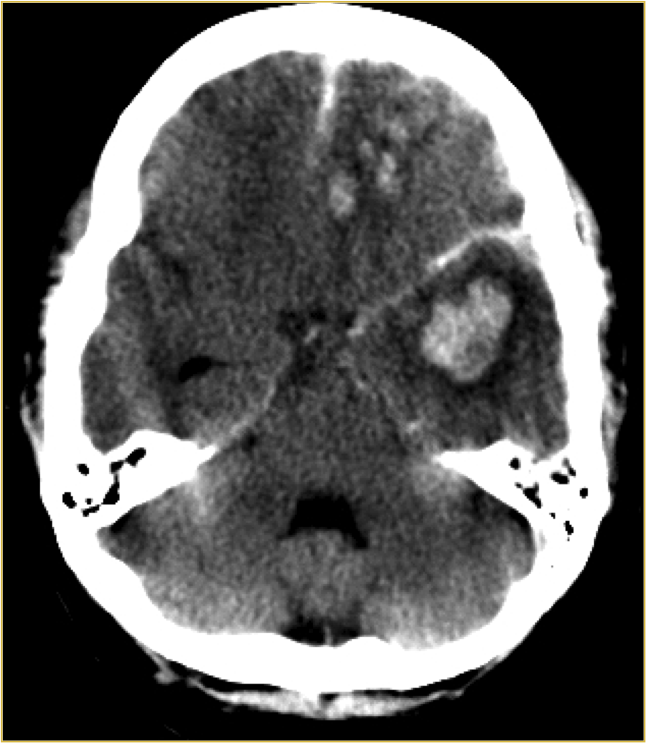

Lesión Axonal Difusa.

Está provocado por un mecanismo brusco de aceleración/desaceleración + fuerzas rotacional que causan ruptura de microvasculatura y de axones (lesiones por cizallamiento en la interfase sustancia gris – sustancia blanca debido a la diferencia de consistencia).

El contexto clínico suele ser el de un paciente con TCE de alta energía que presenta mala evolución, estado comatoso y /o fallecimiento, a pesar de contar con exámenes de TC normales o con muy escasas alteraciones al momento del ingreso. Estos paciente tienen indicación de RM.

Localizaciones:

- Grado 1: Interfase cortico-subcortical (lóbulos frontales y temporales sobre todo)

- Grado 2: Grado 1 + Cuerpo calloso (en el esplenio sobre todo)

- Grado 3: grado 2 + Tronco del encéfalo.

Además la localización cortico-subcortical, el cuerpo calloso es otra localización (esplenio) y normalmente se acompaña de daño axonal difuso también en hemisferios cerebelosos y tronco del encéfalo (regiones posterolaterales de mesencéfalo y protuberancia).

Hallazgos TC:

- En fase aguda puede ser Nomal.

- Edema cerebral (borramiento de surcos)

- Focos hemorrágicos en las sitios anteriomente descritos

- En fase cronica = zonas hipodensas + atrofia.